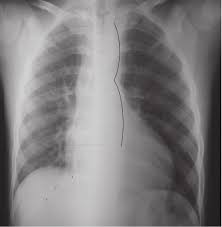

Pronostico en pacientes con coartación aórtica

La coartación aórtica, si no se trata, puede llevar al desarrollo de insuficiencia cardíaca, especialmente en lactantes y personas de mayor edad. La insuficiencia cardíaca ocurre cuando el corazón no…

Tratamiento de la coartación aórtica

El tratamiento de la coartación aórtica es necesario debido a las posibles complicaciones y consecuencias negativas que puede causar esta afección en la salud de una persona: Prevenir la progresión…